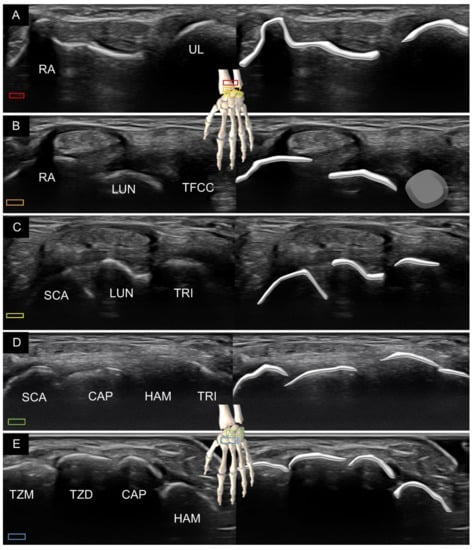

5. Sonoanatomy of Dorsal Extrinsic Carpal Ligaments

Attachment to the Triquetrum

6. Sonoanatomy of Dorsal Intrinsic Carpal Ligaments